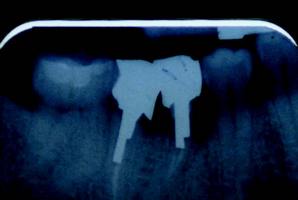

The implant offers an increase of $284 in gross production over the three-unit bridge, which is no big deal. However, you have provided a better and more permanent solution for your patient. Note that this example assumes that no extraction is needed, no site preservation is needed, there is good bone both vertically and horizontally, and adjacent teeth are not in need of restoration–essentially a perfect situation! This rarely presents itself in my practice. So, let’s consider a more realistic example, specifically the case that was presented pictorially in the last article. You may remember the “tired” molar that was failing with a fistula and hemisected roots. In that case, the patient would not entertain any removable solution, so I presented her with these fixed solutions for comparison:

Option 1: Traditional Three-Unit Bridge, $3,319 (including extraction at $121, two retainers at $1,000 each, pontic at $1,000, plus core build-up for distal retainer at $198). Option 2: Single Tooth Implant, $4,753 (including extraction at $121, site preservation $150, implant placement $1,822, abutment $462, crown $1,000; plus core build-up $198 and crown $1,000 to restore distal tooth).